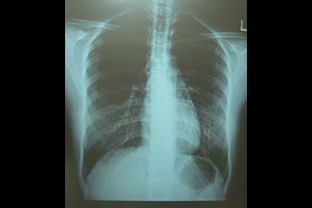

提携病院の協力によりレントゲン撮影し、直接患部を見ます。

内科学的または整形外科学的な診断とともにカイロプラクティックの判断をします。